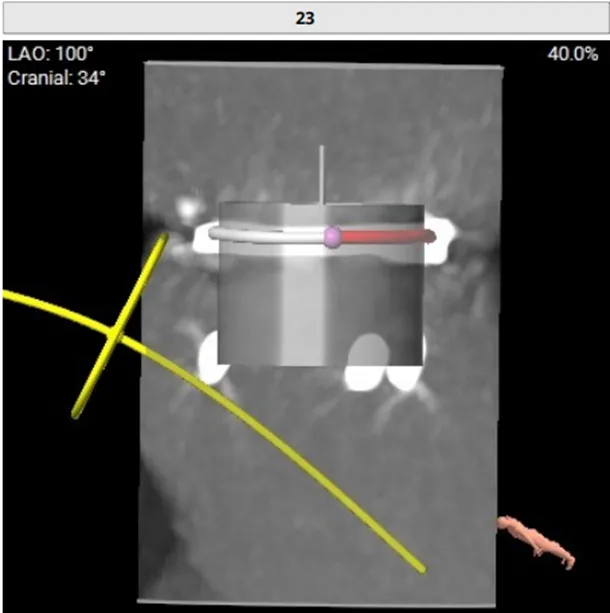

RAO:23° CRA:25°

Positioning heigh: 90/10 preferred